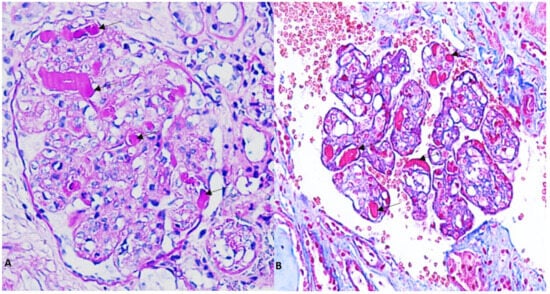

2. Case Presentation